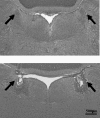

Figure 1. Representative photomicrograph of an electrolytic lesion of the locus coeruleus (LC)

The figure shows coronal sections at the pons level illustrating the location of the LC (upper panel) and a typical LC lesion (lower panel). The arrows indicate either the intact LC or the site of lesion.